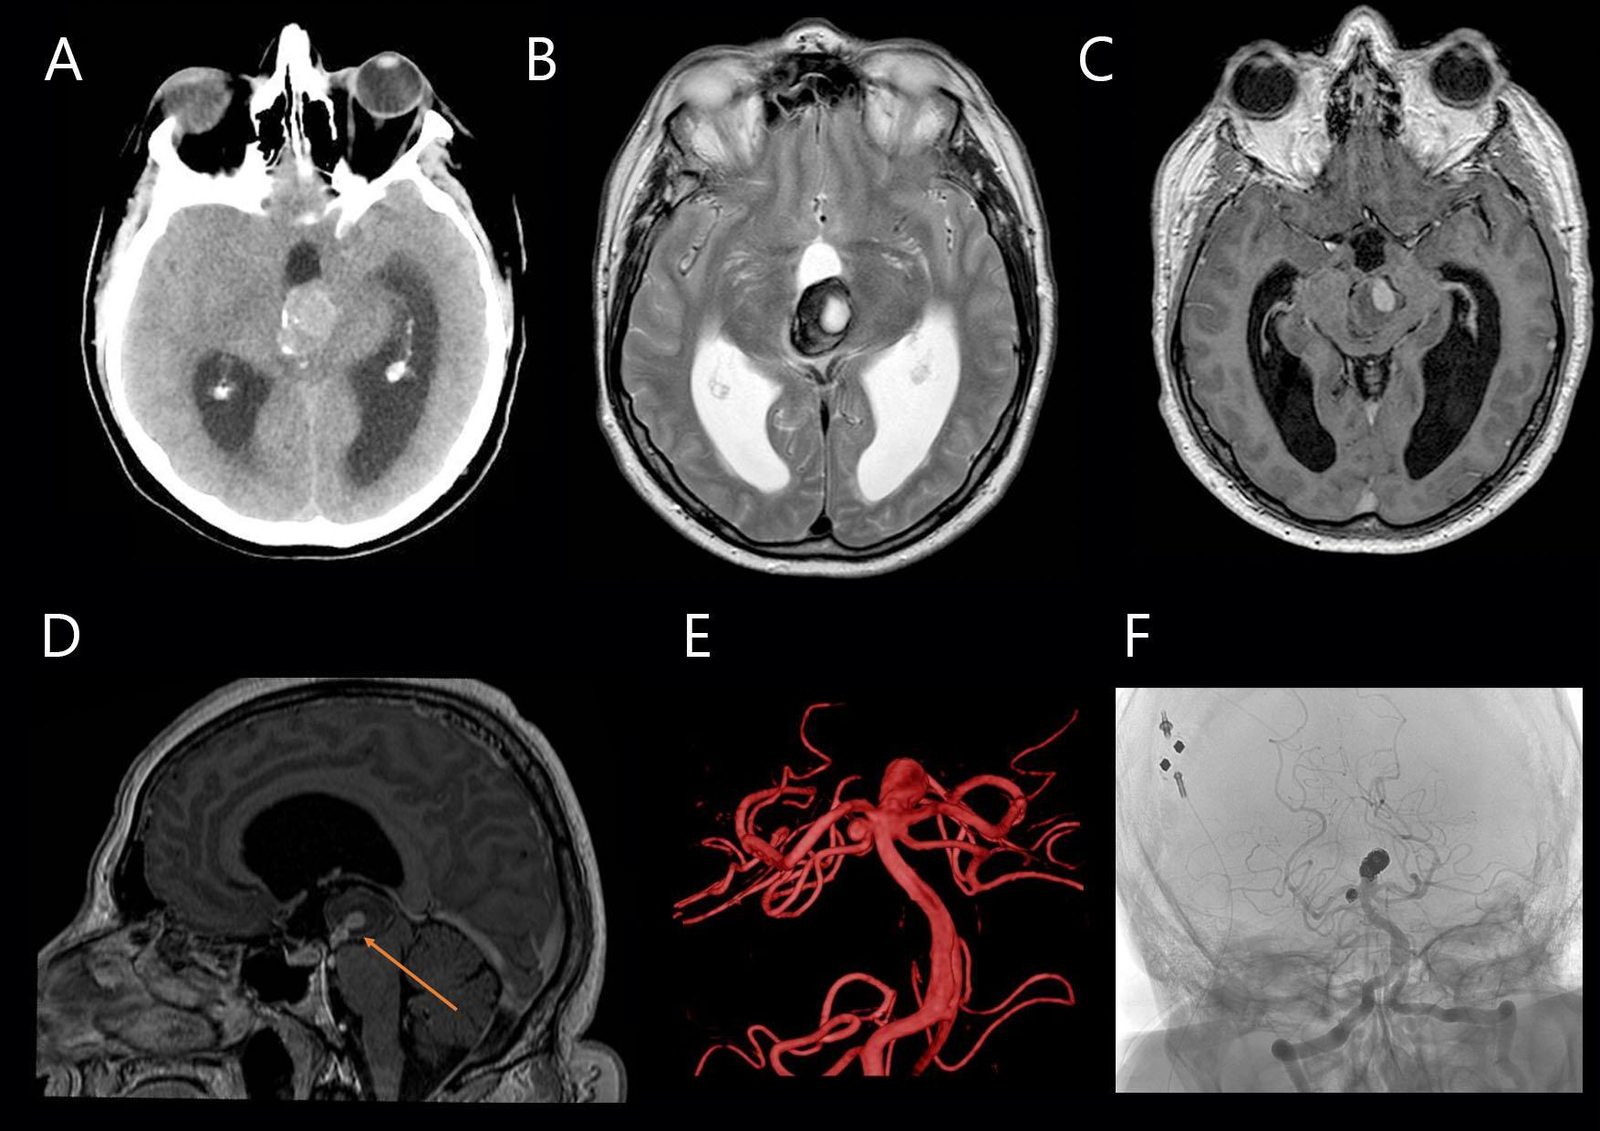

Paciente masculino de 66 años que se presentó al servicio de guardia y urgencias por cuadro clínico caracterizado por mareos de 3 meses de evolución e inestabilidad de la marcha de 24 hs de evolución. Como único signo positivo al examen físico se constató dismetría de miembros superiores. Se decidió estudiar con TC de cerebro en donde se identificó, en topografía pineal y tercer ventrículo, una voluminosa lesión ocupante de espacio, sólida, de aproximadamente 27 x 21 mm de densidad heterogénea, con probable relación a restos hemáticos en distintos estadios evolutivos asociada a calcificaciones periféricas. Presentaba edema perilesional y efecto de masa sobre el mesencéfalo y tálamo izquierdo, con obliteración parcial del acueducto mesencefálico y el tercer ventrículo, condicionando marcada dilatación del sistema ventricular supratentorial con edema transependimario asociado (Fig 1A).

En primera instancia, se interpretó como una lesión de probable origen tumoral con episodio de sangrado agudo asociado. También se propuso la presencia de un cavernoma de mesencéfalo o tálamo, de un quiste/tumor pineal hemorrágico, entre otros diagnósticos diferenciales. La RMN de cerebro con contraste identificó la lesión previamente descrita, heterogénea con áreas hemáticas periféricas y realce central tras la administración de contraste asociado a efecto de masa y edema perilesional (Fig 1 B-D). En un segundo análisis, y con asistencia de la reconstrucción 3D de las imágenes, se reconoció continuidad entre el área de realce de contraste con el extremo distal de la arteria basilar, interpretándose finalmente como un aneurisma del tope de la arteria basilar parcialmente trombosado. Se confirmó el diagnóstico con angiografía cerebral asociado a un segundo aneurisma de 5x3 mm en el nacimiento de la arteria cerebelosa superior derecha (Fig 1E).

Se discutió el caso en forma interdisciplinaria y se decidió tratar ambos aneurismas por la vía endovascular con coils y stent diversor de flujo. Debido a la presencia de hidrocefalia aguda sintomática y la ausencia de hemorragia subaracnoidea se decidió realizar primero la colocación de un shunt ventrículo peritoneal en un primer tiempo quirúrgico teniendo en cuenta la necesidad de la doble antiagregación luego del tratamiento endovascular. El paciente egresó y luego de dos semanas de la colocación del shunt se realizó la embolización de ambos aneurismas con coils de platino y la colocación de stents tipo diversor de flujo con configuración en “Y”. La angiografía de control mostró la oclusión de ambos aneurismas y la permeabilidad de las arterias basilar, cerebelosas y cerebrales posteriores (Fig 1F). El paciente evolucionó favorablemente con mejoría de la sintomatología. Se otorgó el alta sanatorial al 3er día postoperatorio del procedimiento endovascular.

La trombosis espontánea de los aneurismas saculares gigantes ocurre aproximadamente en el 40% de los casos1. Pueden ser sintomáticos secundario a efecto de masa o accidente cerebrovascular. Schubinger et al. han clasificado a los aneurismas intracraneales gigantes en tres tipos distintos: completamente trombosados, parcialmente trombosados y no trombosados2. Los aneurismas gigantes trombosados se suelen evidenciar en tomografía computarizada como masas redondeadas u ovaladas de gran densidad, no homogéneas asociadas a calcificaciones sin realce con el material de contraste. También se encuentra con frecuencia una cantidad significativa de edema alrededor del aneurisma2,3,4. En muchos casos, como lo reportan varios autores3,4,5,6,7, la tomografía computarizada puede no ser suficiente para confirmar el diagnóstico de este tipo de lesiones ya que al generar gran efecto de masa pueden confundirse con lesiones tumorales. A su vez, la angiografía cerebral en aneurismas trombosados o con mínimo flujo suele ser negativa para la detección de los mismos2. Los aneurismas que se encuentran parcialmente trombosados son los de presentación más habitual y muestran el llamado "target sign"3,8. Este signo radiológico de gran valor diagnóstico, evidenciado en la secuencia T1 de resonancia con gadolinio, hace referencia al realce de la pared del aneurisma acompañado de un fuerte realce del contraste de una parte de la cavidad aneurismática (Fig 1D)3,8. En nuestro caso, la TC mostró una gran lesión hemorrágica no homogénea de bordes calcificados de 2,7 cm de diámetro con edema perilesional, y que se prestaba a confusión con un tumor o un cavernoma. El descrito “target sign”, evidenciado en la RMN, con realce de la pared del aneurisma y también realce central de la cavidad aneurismática fue de gran importancia para lograr el diagnóstico final.

Figura 1.

A. Tomografía computada de cerebro simple. Voluminosa lesión ocupante de espacio sólida, de densidad heterogénea con calcificaciones periféricas. Se evidencia efecto de masa sobre el mesencéfalo y el tálamo. B, C y D. RMN de cerebro secuencia T2 (B) y T1 con contraste axial ( C) y sagital (D). Misma lesión ocupante heterogénea con áreas hemáticas periféricas y edema perilesional, que desplaza el piso del tercer ventrículo y el acueducto mesencefálico con dilatación del sistema ventricular supratentorial con edema transependimario. Se visualiza imagen central con realce periférico (target sign) en contigüidad con el extremo distal de la arteria basilar (flecha naranja). E. Angiografía cerebral digital reconstrucción 3D. Se visualiza aneurisma del tope de la basilar de cuello amplio parcialmente trombosado y aneurisma sacular de la arteria cerebelosa superior derecha. F. Angiografía digital selectiva postoperatoria. Se observa oclusión de ambos aneurismas junto con la permeabilidad de las arterias distales dependientes de la arteria basilar y las arterias cerebrales posteriores